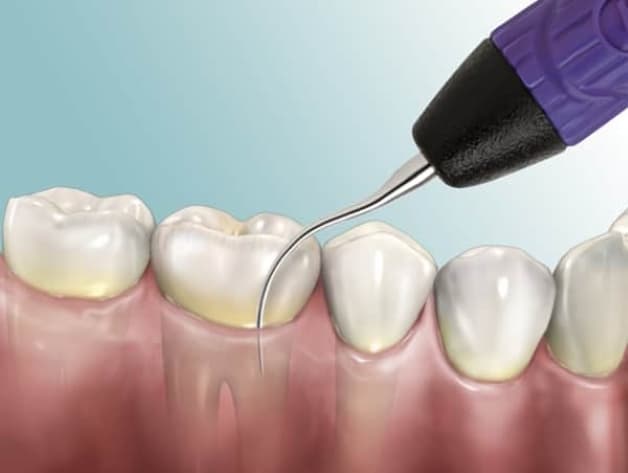

Phương pháp lấy cao răng tại nha khoa được khuyến khích áp dụng

Trên thực tế thì trước mọi tình trạng cao răng, lấy cao răn tại nha khoa vẫn là phương pháp tối ưu, đảm bảo an toàn, hiệu quả. Khi đến nha khoa, bác sĩ sẽ kiểm tra tổng quát để đánh giá tình trạng cụ thể. Sau đó, ta sẽ được thực hiện vệ sinh, lấy cao răng và đánh bóng răng. Tình trạng răng miệng tổng quát cũng sẽ được nắm rõ. Từ đó, bác sĩ sẽ tư vấn thêm về cách chăm sóc răng miệng phù hợp hơn.